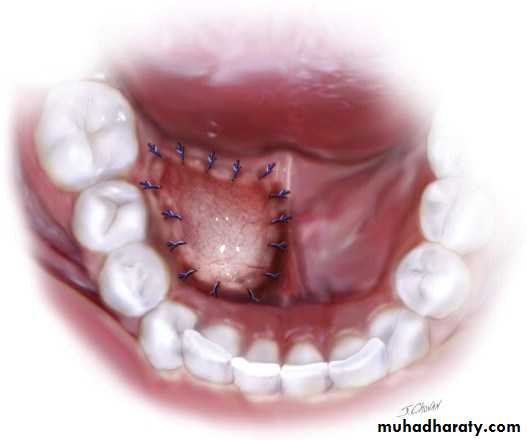

2. The marsupialization

operation by which the cyst is un covered or de roofed and cystic lining made continuous with the oral cavity or surrounding structures. Like surrounding periosteum, and held in place with dressings, if gauze dressings are used. They may be removed in about 7 to 10 days.

Indications for marsuplization of a cyst include: those conditions in which adjacent vital structure such as teeth may be involved if the cystic contents are completely enucleated or danger exists of entering adjacent paranasal sinuses or a marked bone defect is to be avoided. The possible occurrence of paresthesia from surgical trauma or severance of a nerve is also eliminated